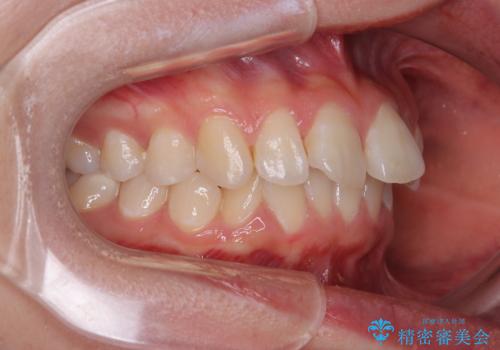

深い咬み合わせによる隙間 インビザライン矯正でコンプレックスを改善

- 上の前歯の隙間を気にして来院された患者様です。

インビザラインにより、上下の歯列を側方に拡大しつつ、前歯の隙間を閉じていくこととしました。

隙間の原因は強い咬合力や舌の突出癖、小帯の異常付着などがありますが、舌のトレーニングをしっかりと行いながら、装着時間を遵守して装着していただいたおかげで、スムーズに治療を終えることができました。